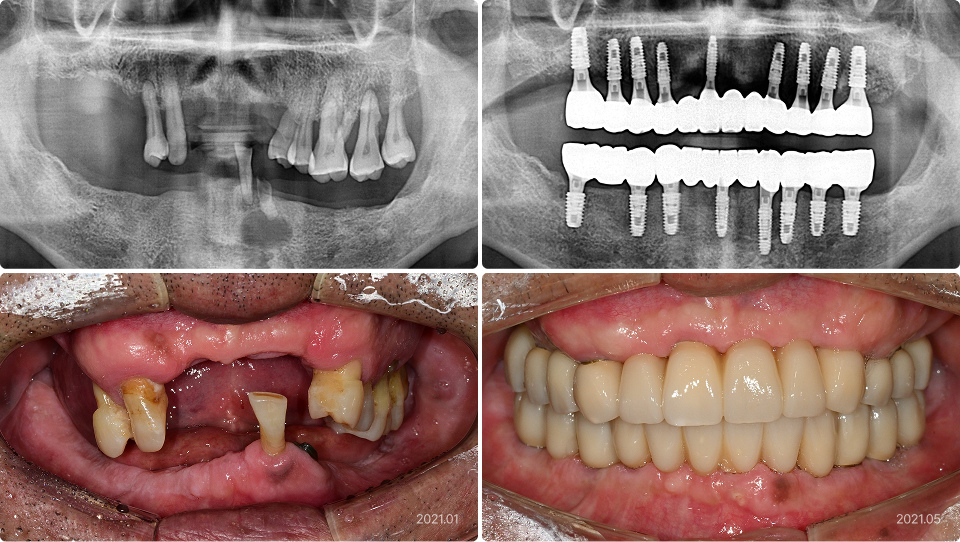

다수의 임플란트를 식립하는 경우

“치아가 거의 없어 전체 임플란트를 해야했는데 엄두가 안났어요.”

치료 전

치료 후

치료 내용

• 다수 치아 발치 및 돌출은 전체 발치 후 임플란트 식립

• 의식하진정법(수면마취)으로 상하악에 17개 임플란트 식립, 씹기 기능 회복

• 1주일에 예비치아 장착, 4개월 만에 최종치아 완성